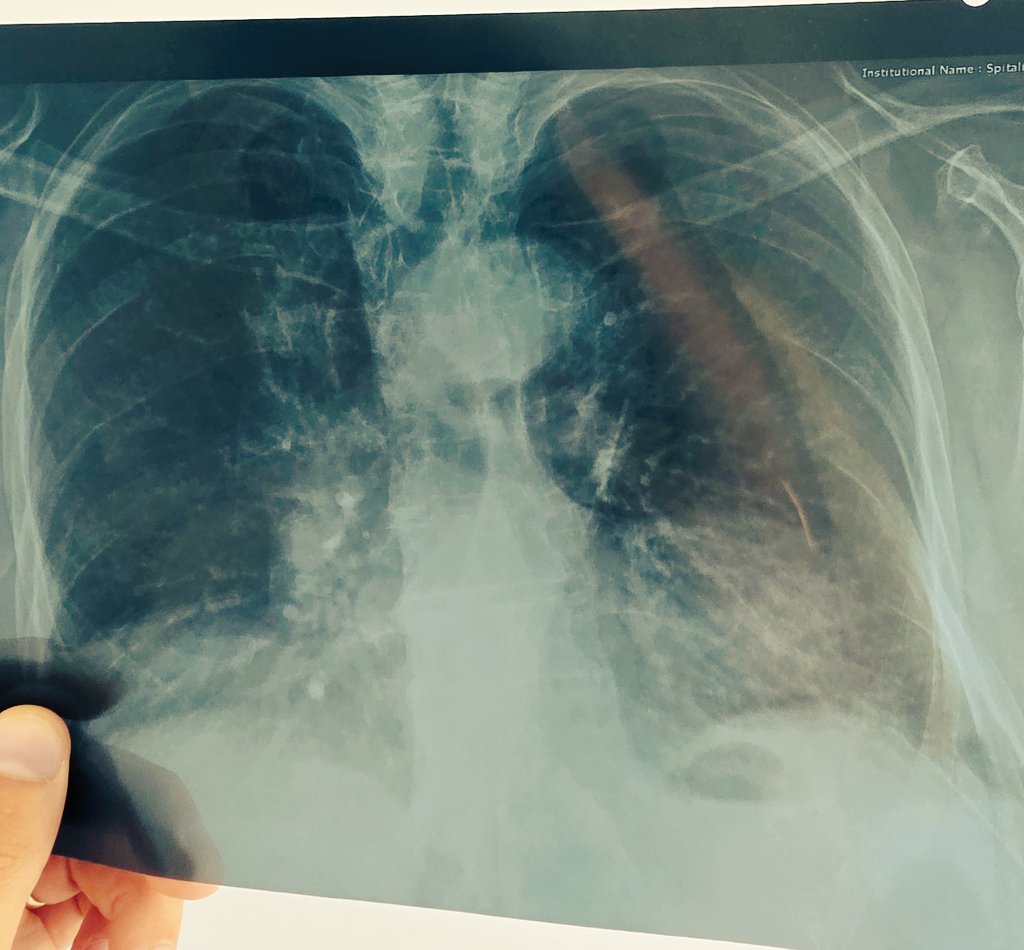

Cardiologist #TTEGURU #ECG #HOLTER